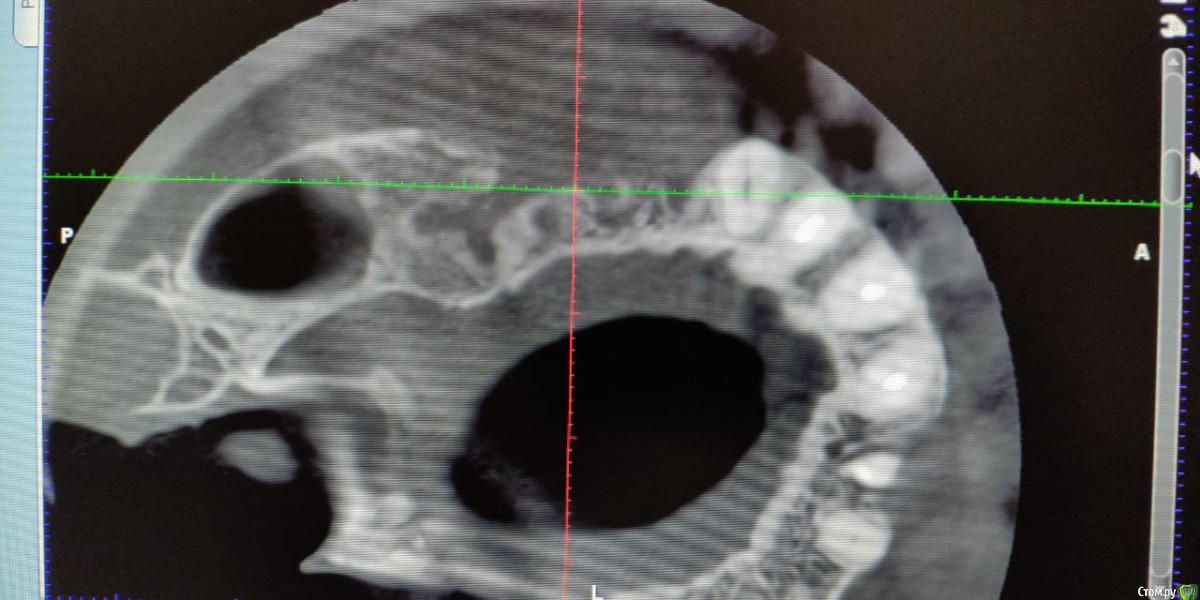

Лералена Опубликовано 14 октября, 2018 Поделиться Опубликовано 14 октября, 2018 Здравствуйте! В июне этого года мне установили 2 имплантата в 1.4 и 1.6 сверху справа, так же был синус-лифтинг в районе 1.6. Через несколько дней после имплантации начался абсцесс в этой области, но доктор списал все на соседний 1.7 зуб и удалил его вместе с имплантатами. После всех манипуляций я выждала 4 месяца и сделала снимки. На консультации другого хирурга мне сообщили, что полностью отсутствует картикальная пластина в области 1.4-1.6, имеется сообщение с синусом, как я поняла отверстие. Эта область немного побаливает при надавливании и вообще, я ее чувствую при разговоре. Уважаемые доктора, подскажите, что мне делать? Как протезироваться? Прежний хирург, проводивший имплантацию, переписал всю мед карту, подделал согласия на вмешательство. Твориться полный беспредел. Ссылка на комментарий

Лералена Опубликовано 14 октября, 2018 Автор Поделиться Опубликовано 14 октября, 2018 https://cloud.mail.ru/public/2sk5/SAPv3y5D1 Это снимки КТ на сегодняшний день, прошло 3.5 месяца после удаления имплантатов и 7 зуба сверху рядом с ними. Ссылка на комментарий

Лералена Опубликовано 17 октября, 2018 Автор Поделиться Опубликовано 17 октября, 2018 Доктора, помогите, пожалуйста. Не знаю как лечиться и идти на повторную имплантацию. Была у двух хирургов, говорят нетбходима сложная операция по восстановлению кости. После через 9 месяцев имплантация и мягкотканая пластика. Ссылка на комментарий